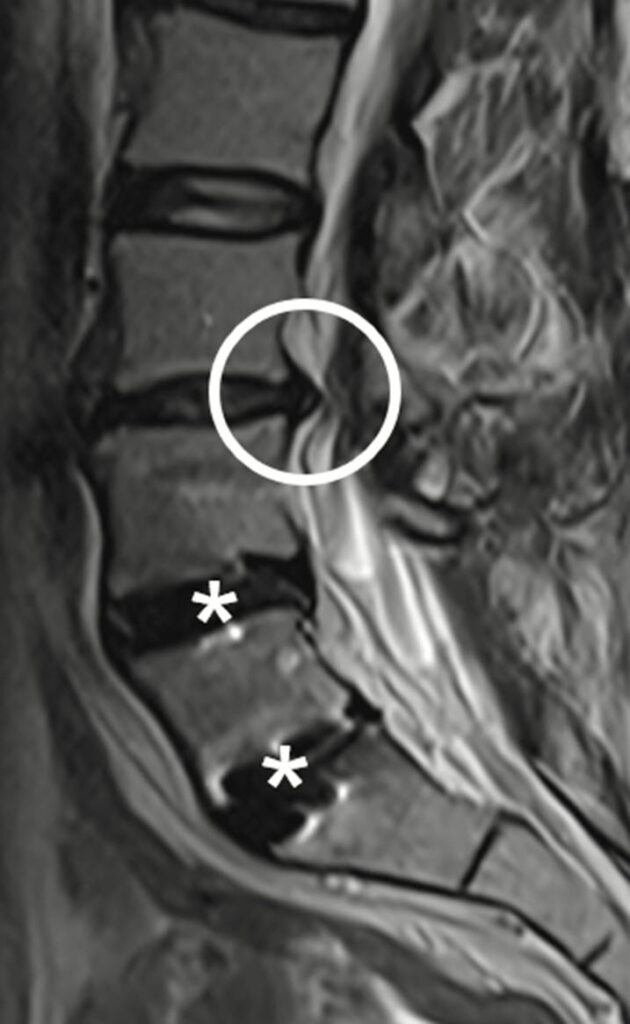

Das MRT eignet sich besonders gut, um frühzeitig Lockerungen von Prothesen oder Schrauben zu erkennen. Es kann feinste Veränderungen an der Knochenstruktur oder an den Implantaten nachweisen, die auf eine Lockerung hinweisen könnten.

Diagnostik von Vernarbungen und Infektionen

Das 0.55 Tesla MRT kann Narbengewebe nach Operationen oder Entzündungen, die durch Infektionen oder Abrieb verursacht wurden, gut darstellen. Dies ist entscheidend, um Infektionen oder Komplikationen frühzeitig zu erkennen und entsprechend zu behandeln.